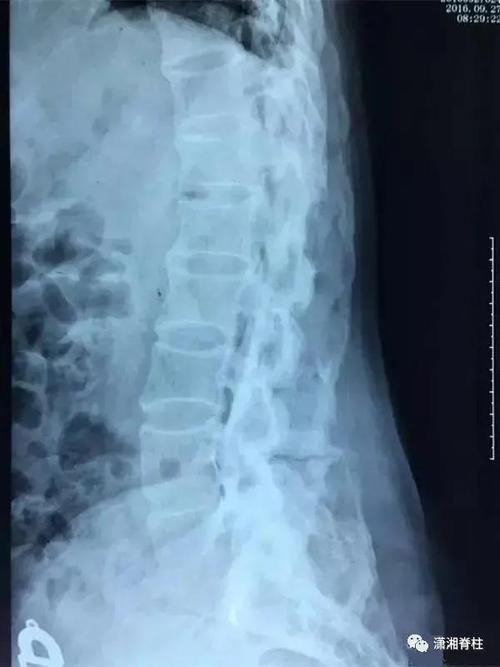

起病隐袭。强直性脊柱炎患者逐渐出现臀髋部或腰背部疼痛和/或发僵,尤以卧久(夜间)或坐久时明显,翻身困难,晨起或久坐起立时腰部发僵明显,但活动后减轻。有的患者感臀髋部剧痛,偶尔向周边放射。疾病早期疼痛多在一侧呈间断性,数月后疼痛多在双侧呈持续性。随病情进展病变由骶髂关节向腰椎、胸颈椎发展,则出现相应部位疼痛、活动受限或脊柱畸形。据报道,我国患者中大约45%的患者是从外周关节炎开始发病。

24%~75%的AS患者在病初或病程中出现外周关节病变,以膝、髋、踝和肩关节居多,肘及手和足小关节偶有受累。非对称性、少数关节或单关节,及下肢大关节的关节炎为本病外周关节炎的特征。我国患者除髋关节外,膝和其他关节的关节炎或关节痛多为暂时性,极少或几乎不引起关节破坏和残疾。髋关节受累占38%~66%,表现为局部疼痛,活动受限,屈曲孪缩及关节强直,其中大多数为双侧,而且94%的髋部症状起于发病后头5年内。发病年龄小,及以外周关节起病者易发生髋关节病变。